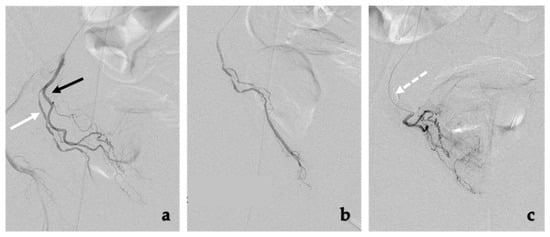

4.2. Procedure